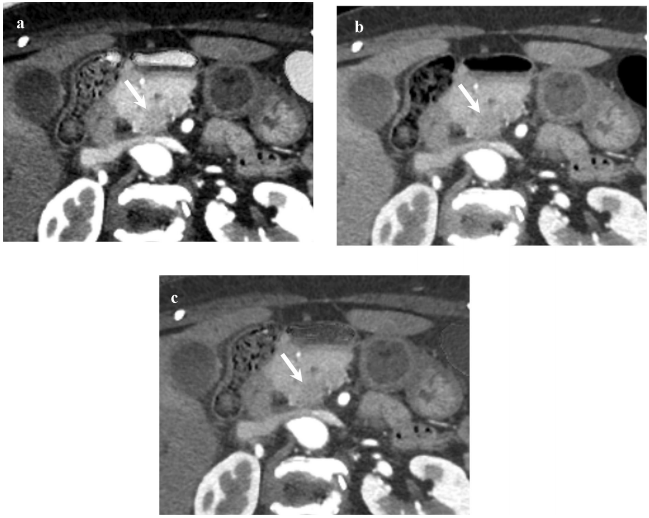

诊断信心改善:专家组的"不确定"诊断比例从24%降至9%,整体诊断信心评分显著提高(P<0.001)。图3案例显示硅/鸟粪石图像使肿瘤显影更清晰。